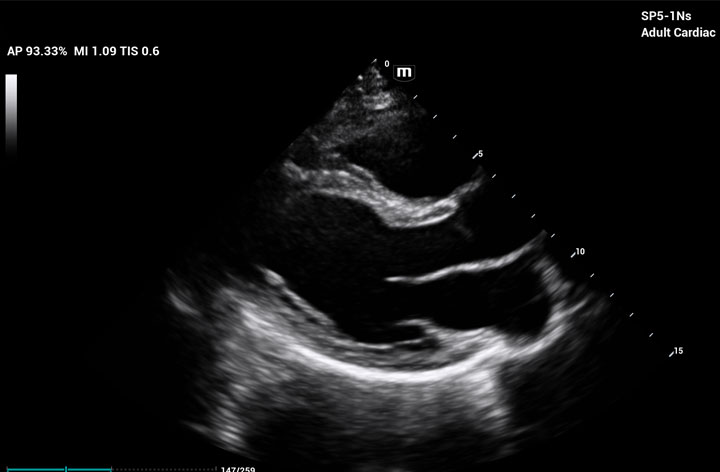

The ME8 Ultrasound System has been thoughtfully designed to overcome the obstacles clinicians face in today’s challenging healthcare environment. Powered by our groundbreaking software-based beamformer technology, ZONE Sonography® Technology+(ZST+), the ME8 Ultrasound System empowers decision-making by providing end-users best-in-class image quality and access to a comprehensive suite of workflow enhancement tools.